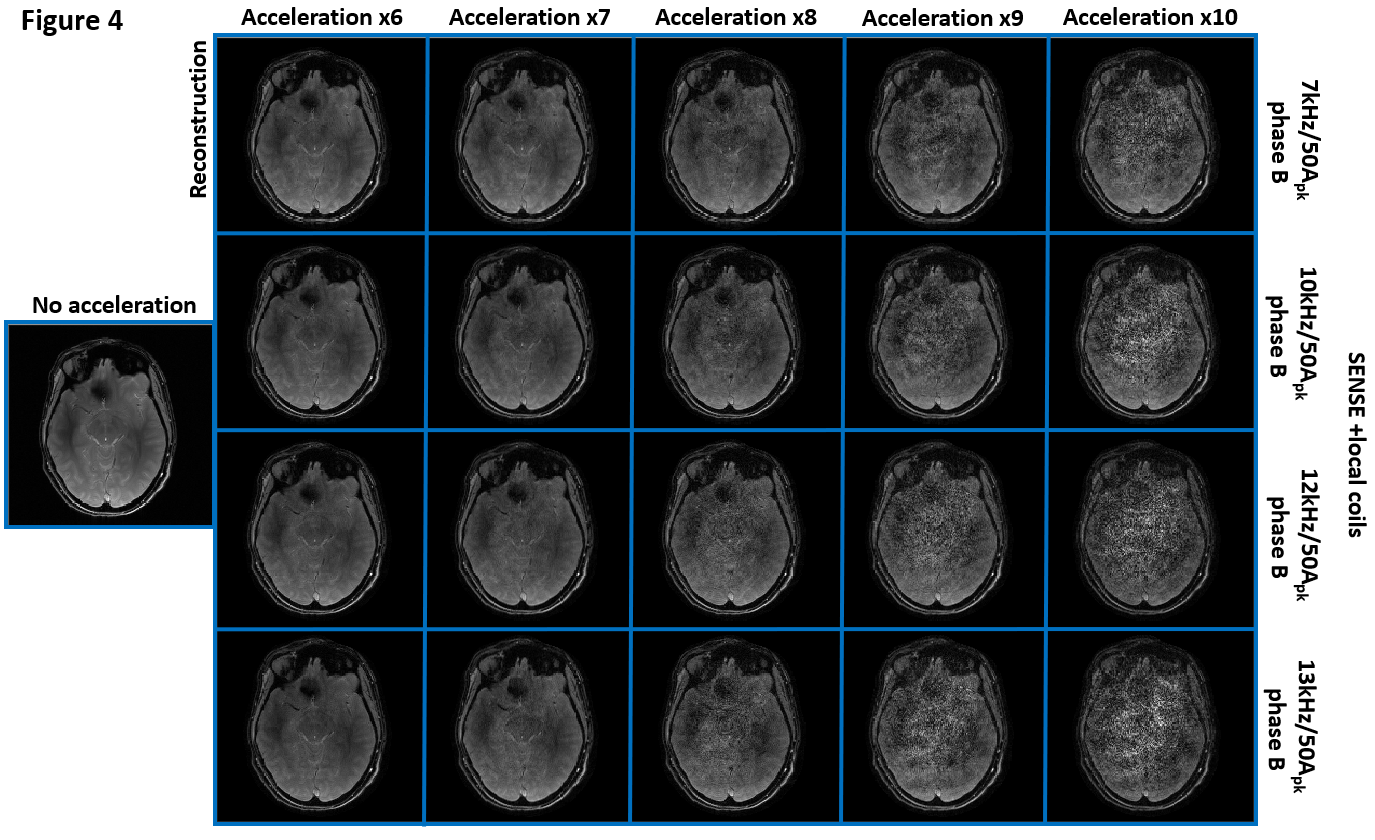

3. Figure 4, 5. High bandwidth: 380 Hz/Pixel. Local coils: 7kHz, 10kHz, 12kHz, and 13kHz, all with 50Apk and the phase pattern B.

In Figure 4 and 5, sinusoidal modulations in higher frequencies were compared. For the acceleration factor equal to or above 8, both the reconstructed images and the G maps demonstrate the SNR advantages for the relatively lower modulation frequency. Additionally, the current peak value was reduced to 45A for the 10kHz, and 40A for the 12kHz and the 13kHz, due to the damping of the power amplifier equal to or above 10kHz.

Figure 4. The reconstructed images with local B0 modulations in varying frequencies, given higher scanner bandwidth (380Hz/Pixel). As the acceleration factor increased, the reconstruction in lower modulation frequency gradually showed advantages in SNR efficiency. The SNR amplification was generally higher compared to identical modulation frequencies given lower scanner bandwidth. Note that such a result is a mixed effect of different encoding patterns and different levels of current damping by the power amplifier.